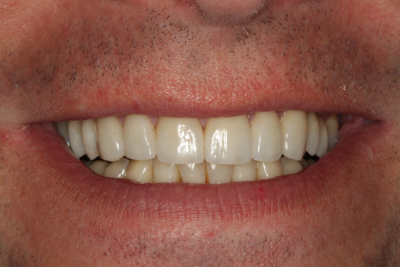

Esthetics, phonetics, and functionを確認した後、最終的な修復を行う準備が整いました。 プロビジョナルレストレーションの写真と印象がラボに渡され、プロビジョナル段階で調整した審美性と咬合を複製し、Darrenの最終修復物に情報を伝達しました。 納品日までに、すでに機能的な問題を診断・治療し、プロビジョナルで治療計画を検証しています。

私たちの目標のひとつは、下顎前歯の準備をせずに、適切な前歯部誘導を達成することでした。 幸いなことに、矯正とダイレクトボンディングの組み合わせで十分すぎるほどの結果が得られたので、今回は下顎弓の修復を見送ることができました。 繰り返しになりますが、私たちの目標は、可能な限り最良の結果を得るために、最小限の歯科治療を行うことです。 時には、包括的な歯科治療を行うために、かなりの量の治療を行うこともありますが、できるだけ多くの歯質を保存するために、保守的であることに挑戦することが重要なのです。

ダレンとの協力により、咬合安定の5つの要件を得るために必要な治療を提供することができました。 現在、彼はすべての歯で安定したストップ、機能の包絡線と調和した前方誘導、前歯が突出した場合の即時後方排除、および作業側と平衡側の突出の干渉をもはや持っていない。